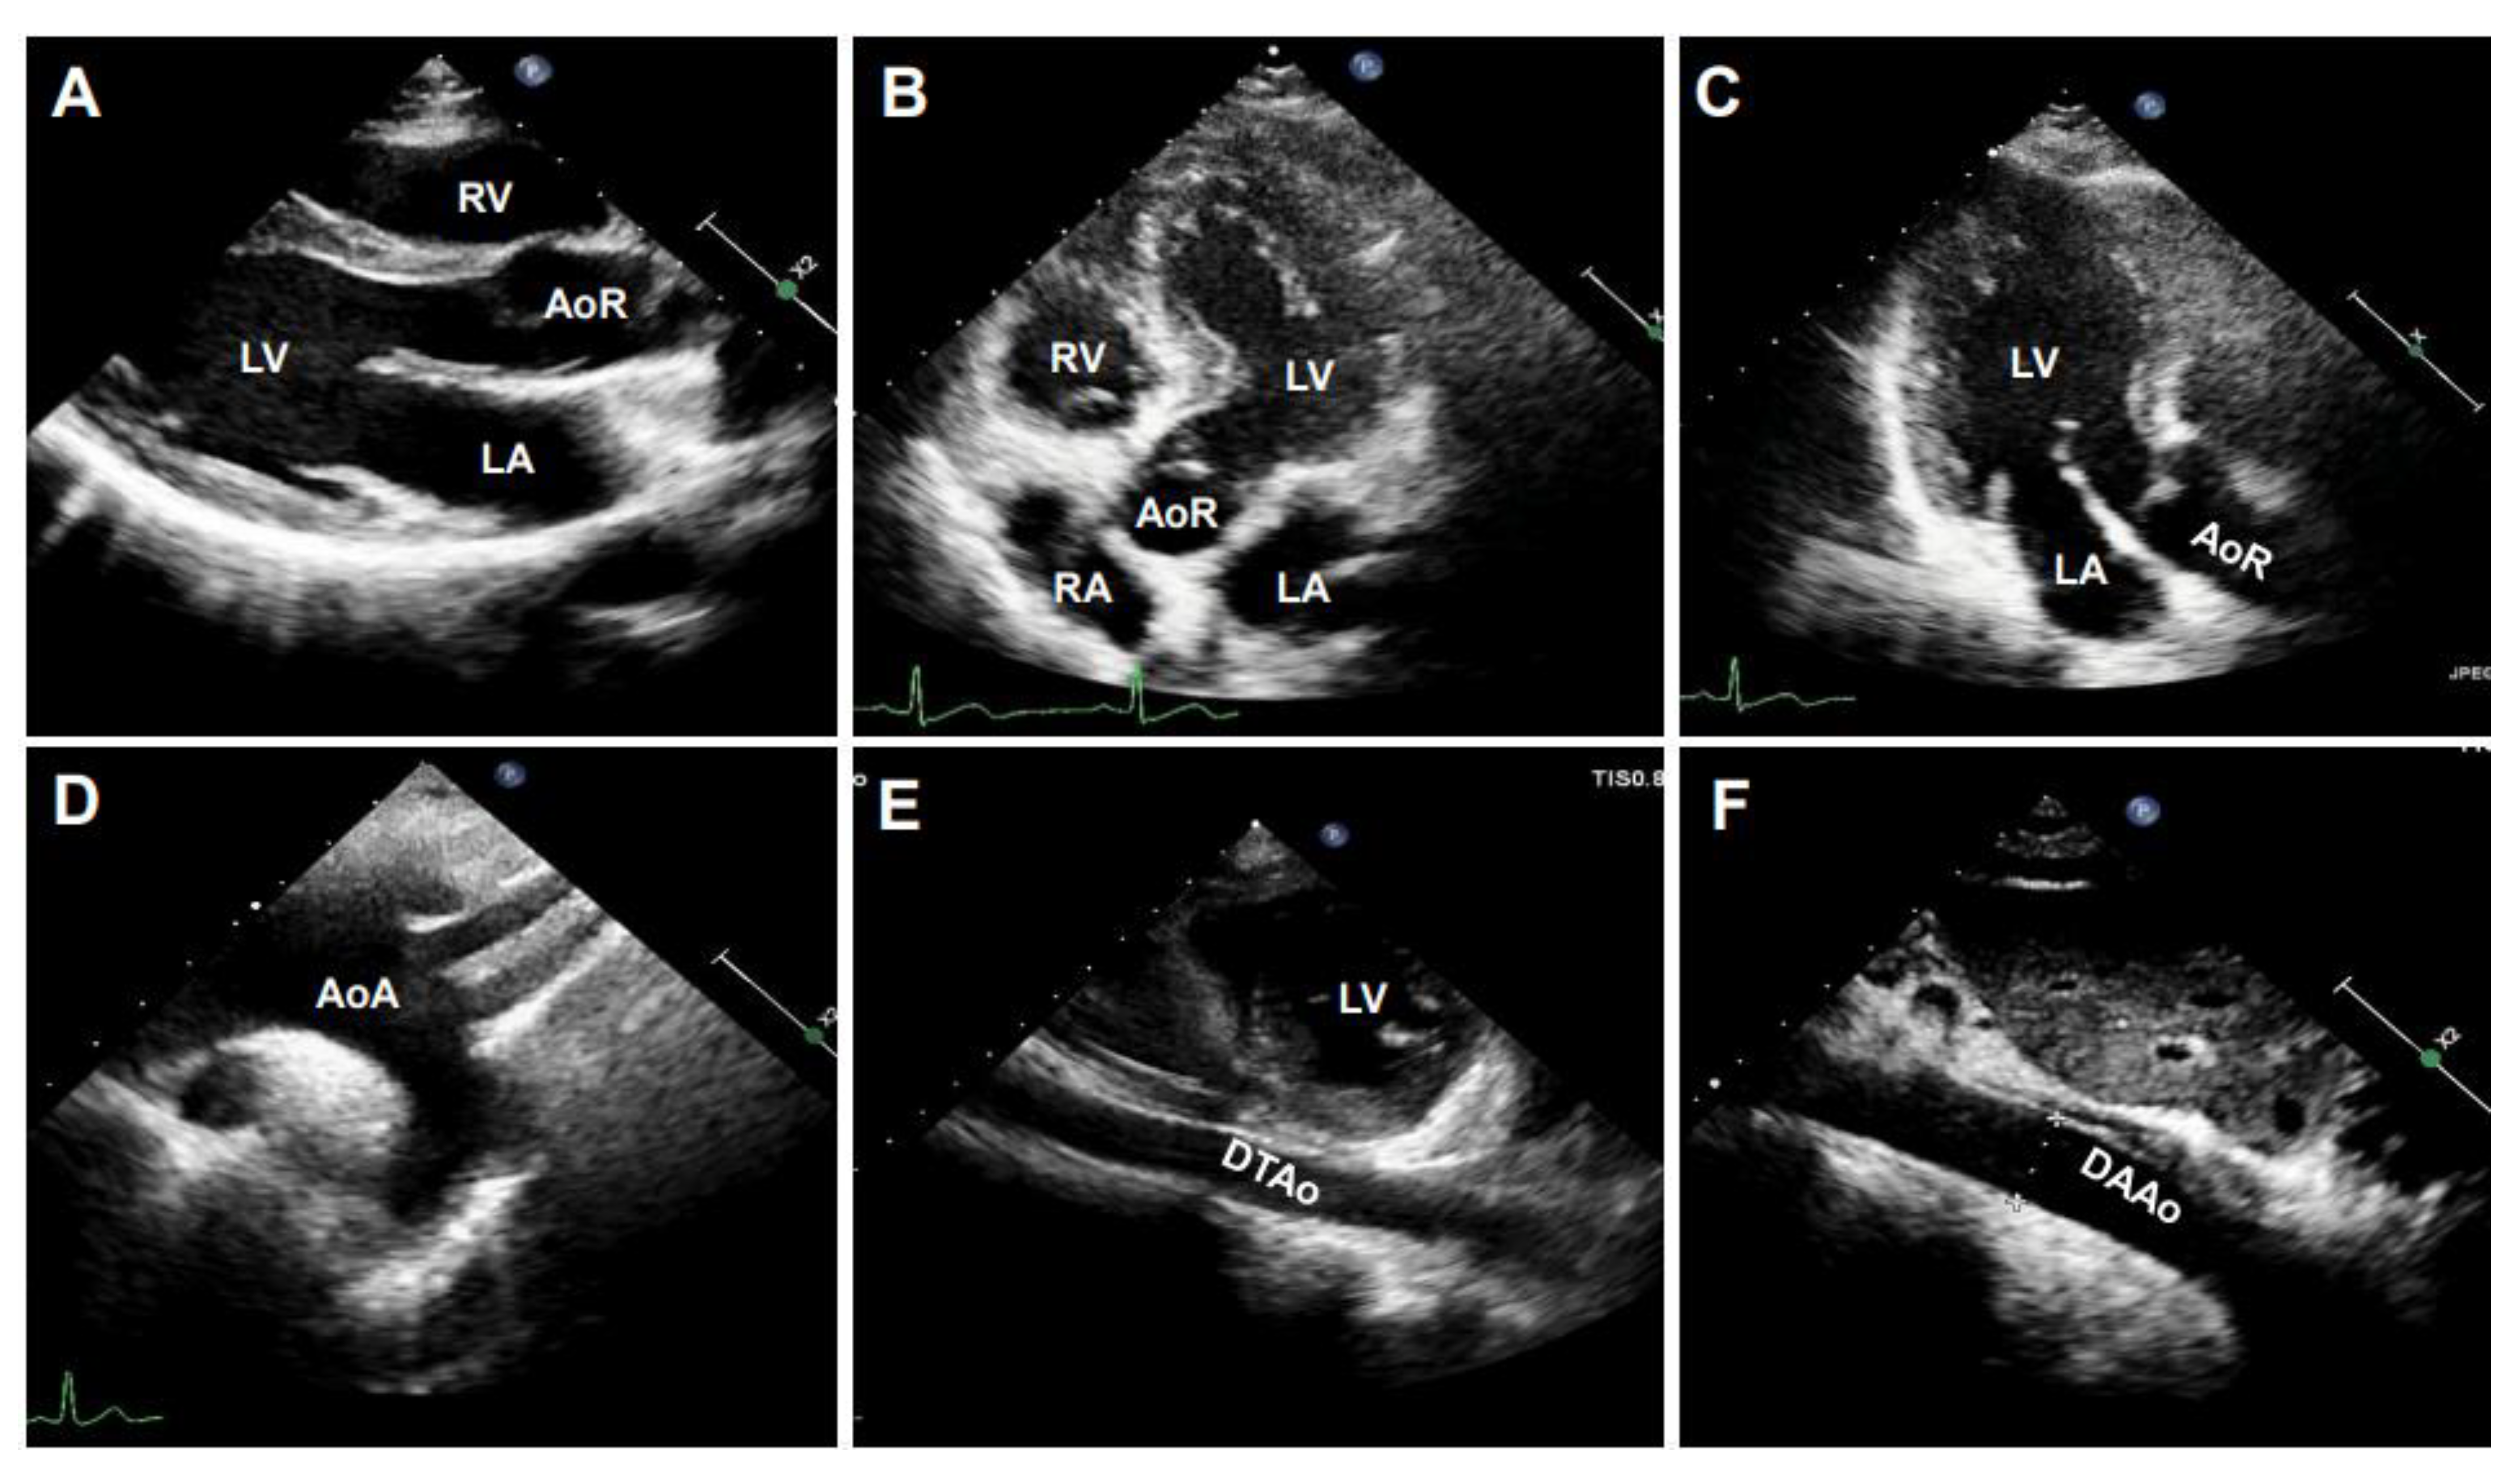

STI is another newly developed ultrasonographic method used to quantify the tissue wall’s deformation of subsurface structures with high spatial resolution. The speckle pattern can be tracked consecutively from frame to frame and ultimately resolved into angle-independent 2D and three-dimensional (3D) strain-based sequences, providing both quantitative and qualitative information regarding tissue deformation and motion. So far, speckle tracking using in-vessel deformation has been limited to 2D-STI, while the application of 3D-STI in vessels is still undergoing technological developments. 2D-STI can be obtained by B-mode, and the corresponding circumferential strain rate can be calculated by using the dedicated software. Based on frame-by-frame tracking of tiny echo-dense speckles within the tissue, 2D-STI enables the calculations of motion and deformation variables, such as velocity, displacement, strain, and strain rate, through the assessment of the tissues’ lengthening and shortening [43,61]. As illustrated in the upper panel of Figure 9, with a 2D ultrasonographic image of the human aorta, a line was manually drawn along the inner side of the DAAo circumference, and the additional lines within a 15-mm-wide region of interest would be automatically generated by the software (Automated Cardiac Motion Quantificationᴬ⋅ᴵ, Qlab 13.0; Philips Healthcare, Amsterdam, The Netherlands). The shape and width of the regions of interest could be manually adjusted. A cine loop preview feature allowed visual confirmation that the internal line followed the vascular expansion and recoil movements throughout the cardiac cycle. Based on these measurements, the circumferential strain rate can be automatically or semi-automatically calculated by the software, as shown in the lower panel of Figure 9.

Figure 9. The illustration of human aortic assessments by two-dimensional (2D) speckle tracking. Intraoperative 2D speckle tracking analysis from a short-axis view of descending abdominal aorta (DAAo) in a healthy individual. The circumferential strain profile is displayed on a positively directed curve with a peak value of 18.3%.